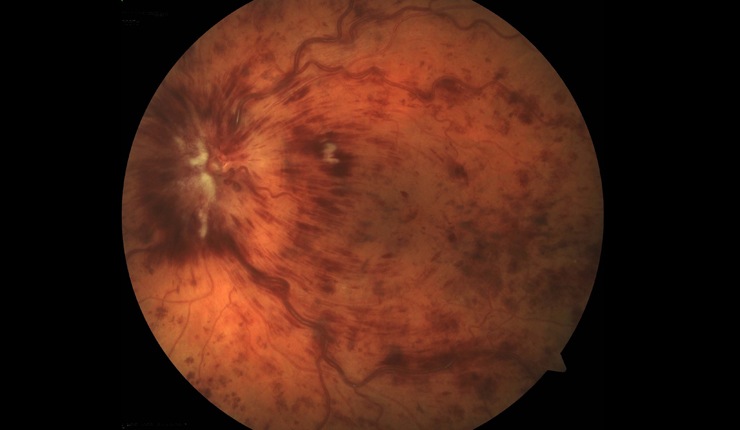

OCT radial scan display showing arcade pattern of fluid associated with branch retinal vein occlusion.